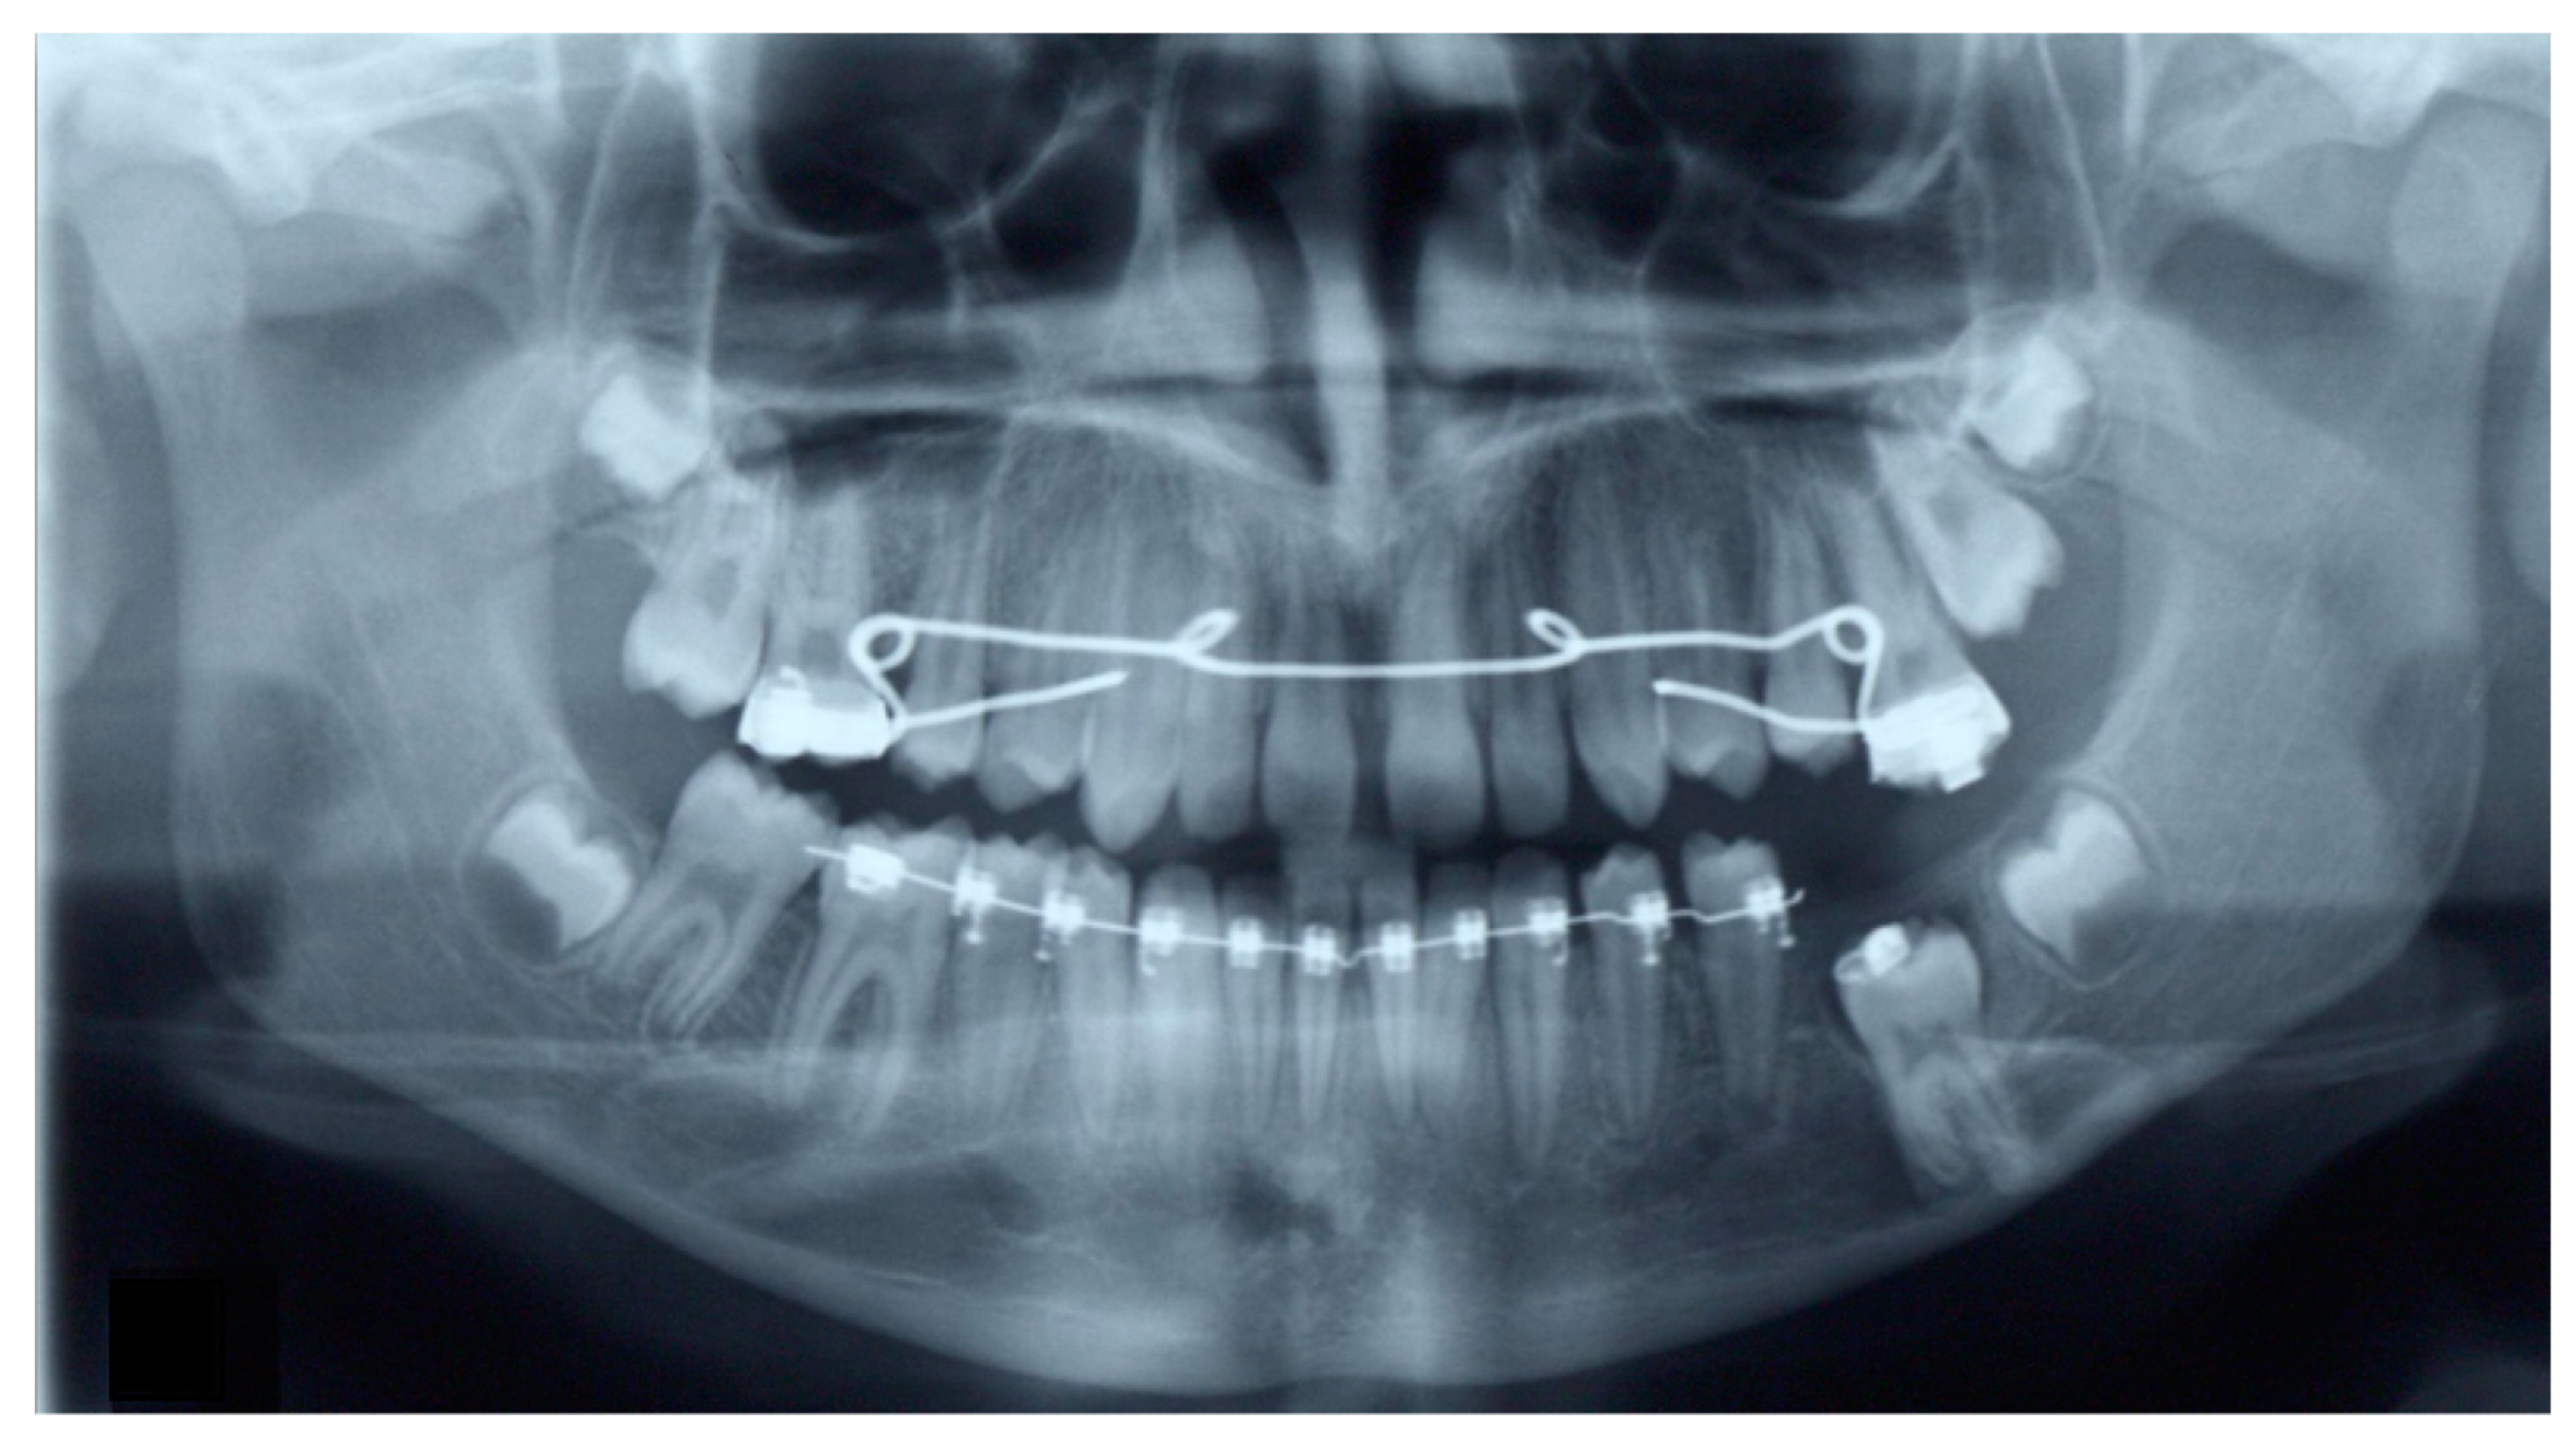

2. Case Presentation